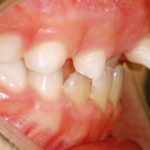

Scopo del presente lavoro è descrivere un caso clinico in cui è stato necessario servirsi dell’ortodonzia per risolvere un problema di natura parodontale: in...